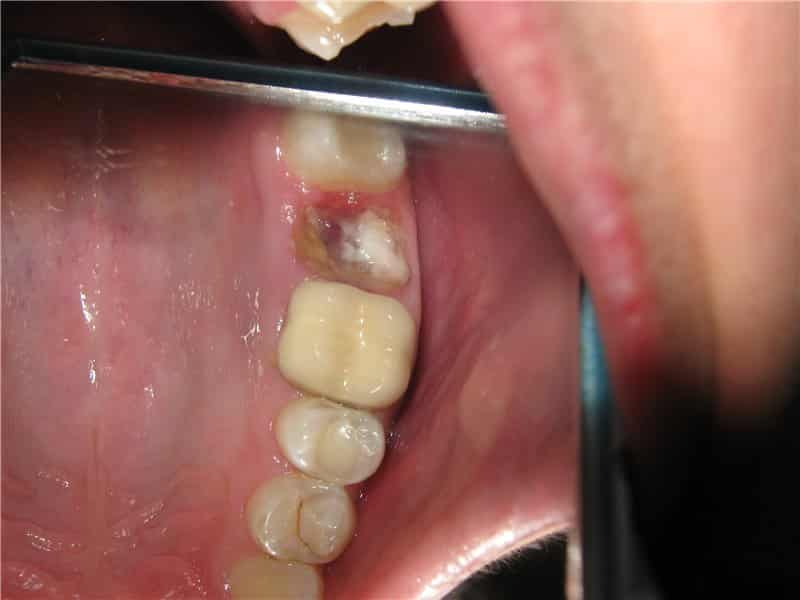

Однако, удаление зубов иногда может сопровождаться неприятными осложнениями, такими как альвеолит. Альвеолит характеризуется воспалением десны и накоплением гнойных выделений в лунке после удаления зуба. Обычно, признаки гнойного воспаления десны после удаления зуба можно заметить в течение нескольких дней.

Небольшое покраснение и отек десны после операции являются нормальными. Однако, если эти симптомы продолжаются более 5 дней и сопровождаются сильной болью, повышенной температурой, гнойным выделением, кровотечением и неприятным запахом изо рта, это повод для беспокойства. Нельзя надеяться, что проблема решится самостоятельно. В таких случаях необходимо незамедлительно обратиться к стоматологу.

Альвеолит: Помимо покраснения и отека лунки, обычно возникают острые боли, кровотечение и накопление гнойных выделений. Альвеолит может также сопровождаться плохим самочувствием, включая повышение температуры, дрожь, мигрени и ощущение общей слабости.